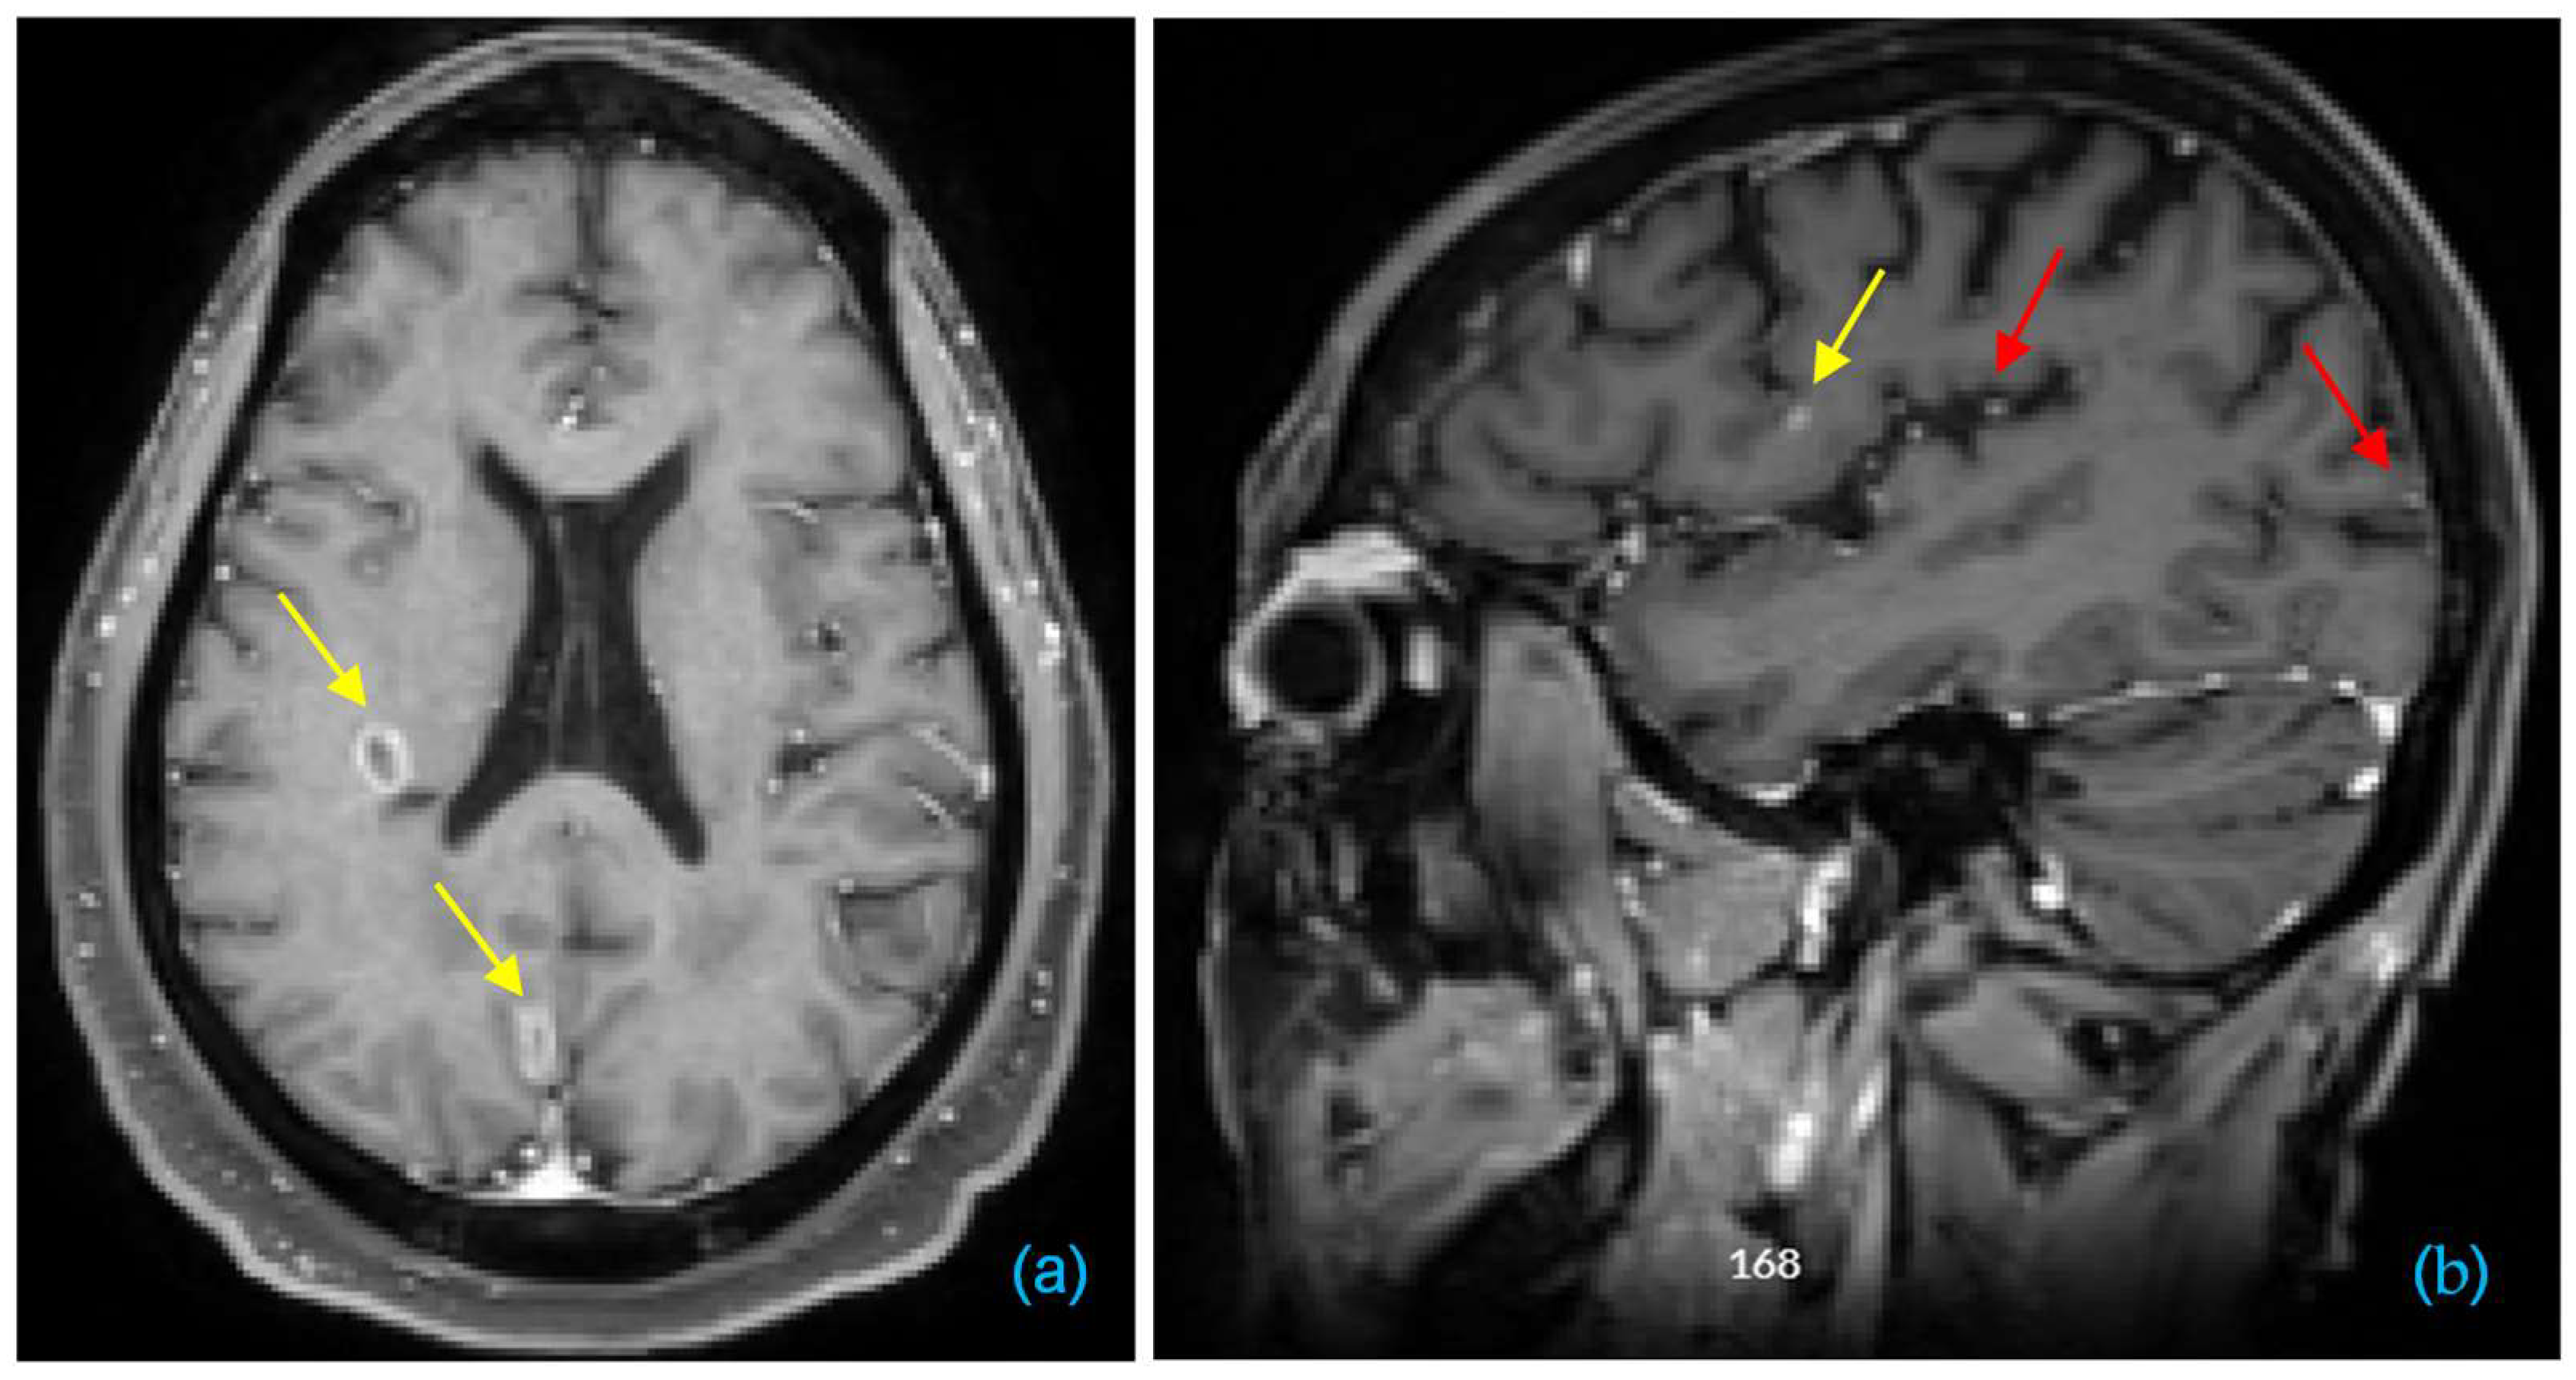

- Fink, K.R.; Fink, J.R. Imaging of brain metastases. Surg. Neurol. Int. 2013, 4 (Suppl. 4), S209–S219. [Google Scholar] [CrossRef]

- Pope, W.B. Brain metastases: Neuroimaging. Handb. Clin. Neurol. 2018, 149, 89–112. [Google Scholar] [CrossRef] [PubMed]